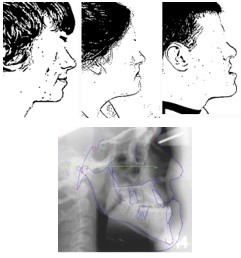

antero-posterior skeletal relationship for class III

*All have class III incisor relationship

Left is class I skeletal

Middle is moderate class III

Right is class III skeletal with OB *

Aetiology could be due to

* Small maxilla

* Large mandible

* Combination of both (most)